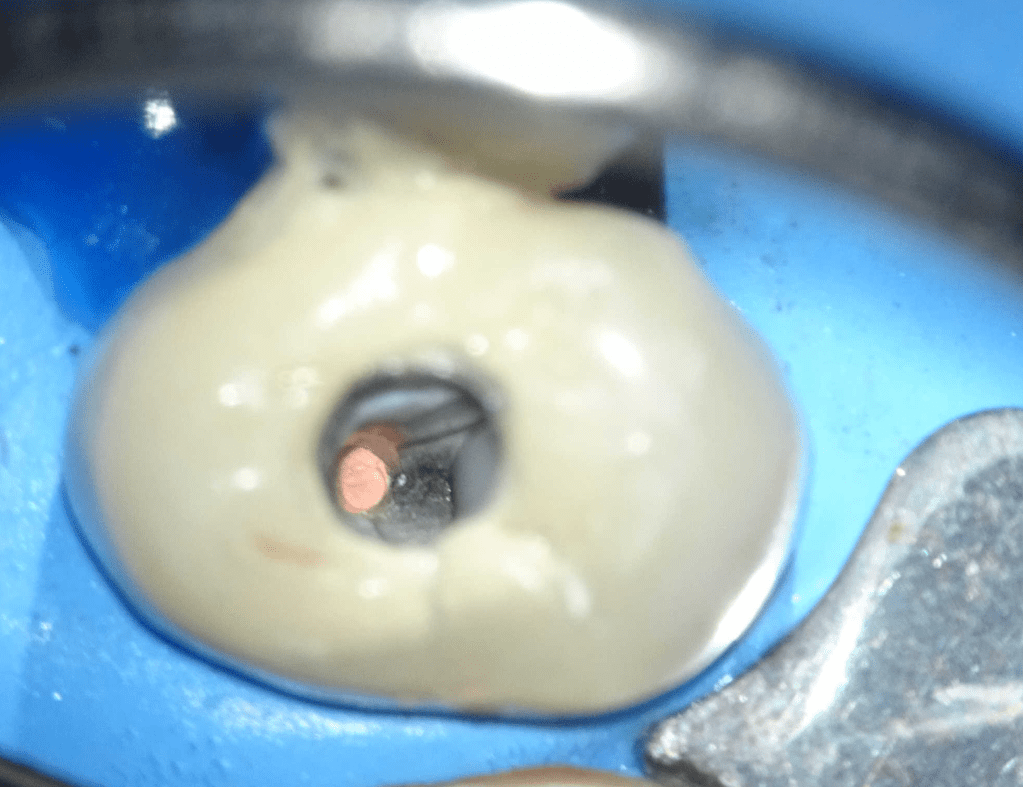

Endodoncias a traves de coronas

20 molar superior a traves de corona